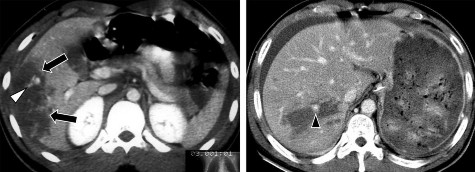

Hình 1.23. Chụp CLVT tiêm cản quang, nhiều vết rách và tụ máu nhu mô gan.

Hình 1.24. Phim chụp lại thấy khối tụ máu dưới bao mới phát triển do chảy máu muộn (mũi tên).

Nguồn: Shanmuganathan K, Mirvis SE [21].

Áp xe gan hoặc quanh gan: Tỷ lệ 0,6% đến 4% [20, 28]. Trên phim chụp CLVT trước và sau tiêm thuốc cản quang, ổ áp xe là khối tỷ trọng dịch, trong

lòng có thể có hơi. Thành khối áp xe bắt thuốc cản quang, đường viền giảm tỷ trọng do phù nề tổ chức xung quanh.

Hình 1.25. Áp xe gan sau CTG trên phim chụp CLVT (mũi tên).

Giả phình động mạch gan: Phình động mạch gan do tổn thương động mạch thông vào nhu mô gan và được tổ chức xơ bao bọc lại, tỷ lệ được báo cáo là khoảng 1% [10]. Chụp CLVT trước và sau tiêm thuốc cản quang, tổn thương là một ổ tròn khu trú, ngấm thuốc mạnh và đồng thời cùng động mạch chủ.

Hình 1.26: Giả phình động mạch gan (mũi tên).

(Trên phim CLVT/ Phim chụp mạch trước khi nút/ Sau điều trị)